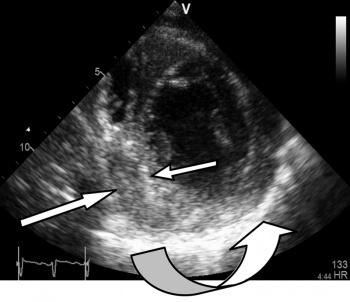

Figure 5: Short axis view showing a thickened hyper-echoic pericardium especially between 4 and 7 o’clock (curved arrow). Organised thick effusion indenting the infero-septal left ventricular wall between 6 and 9 o’clock (straight arrows)

Figure 5: Short axis view showing a thickened hyper-echoic pericardium especially between 4 and 7 o’clock (curved arrow). Organised thick effusion indenting the infero-septal left ventricular wall between 6 and 9 o’clock (straight arrows)(click to enlarge)

Surprisingly the echocardiogram showed a large pericardial effusion containing thick viscid heterogenous fibrin rich exudate with evidence of septation loculation, and organisation, indicating that these changes were not acute. There was Doppler evidence of pericardial constriction; however, the absence of bi-atrial enlargement suggested that it might be fairly recent.

LV and RV function were moderately impaired with EF of 30-40% due to a combination of adhesion and tethering and constriction, hence the compensatory tachycardia to maintain cardiac output.